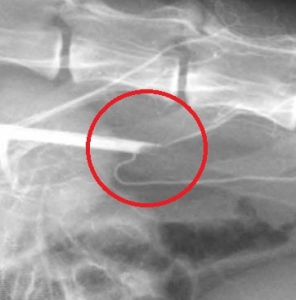

次の写真は、上写真の赤矢印先の塞栓部位の拡大像です。